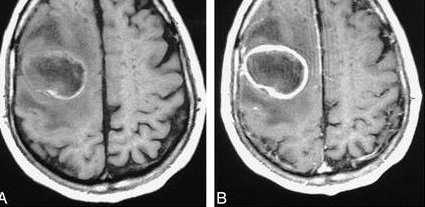

МРТ головного мозга — более точный метод диагностирования. При проведении МРТ на первых стадиях формирования абсцесса мозга (1-9 сутки) энцефалитический очаг выглядит: на Т1-взвешенных изображениях — гипоинтенсивным, на Т2-взвешенных изображениях — гиперинтенсивным. МРТ на поздней (капсулированной) стадии абсцесса головного мозга: на Т1-взвешенных изображениях абсцесс выглядит, как зона пониженного сигнала в центре и на периферии (в зоне отека), а по контуру капсулы сигнал гиперинтенсивный. На Т2-взвешенных изображениях центр абсцесса изо- или гипоинтенсивный, в периферической зоне (зоне отека) гиперинтенсивный. Контур капсулы четко очерчен.